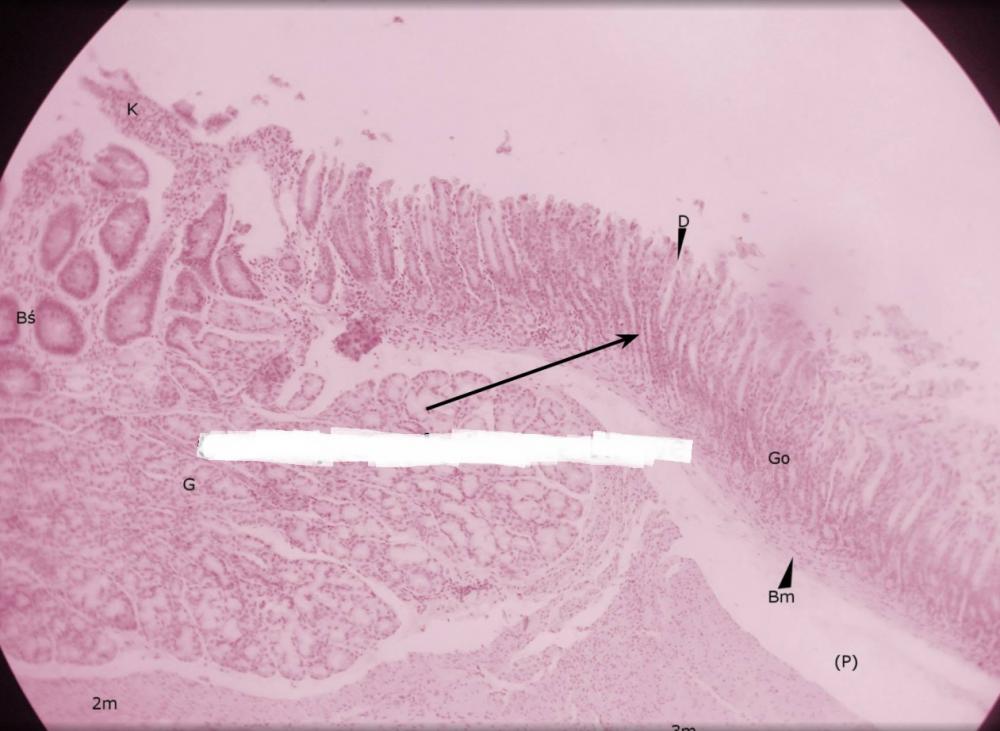

dołki żołądkowe (przejście żołądka w dwunastnicę)

pólka żołądkowe (przejście żołądka w dwunastnicę)

rozgałęzione gruczoły cewkowe - odźwiernikowe (przejście żołądka w dwunastnicę)

kosmek jelitowy (przejście żołądka w dwunastnicę)

krypta jelitowa (przejście żołądka w dwunastnicę)

gruczoły Brunnera (przejście żołądka w dwunastnicę)

błona mięśniowa, składająca się z warstwy okrężnej o podłużnej (przejście żołądka w dwunastnicę)

miejsce po błonie podśluzowej (przejście żołądka w dwunastnicę)

blaszka mięśniowa błony śluzowej (przejście żołądka w dwunastnicę)

gruba, trójwarstwowa mięśniówka żołądka (przejście żołądka w dwunastnicę)